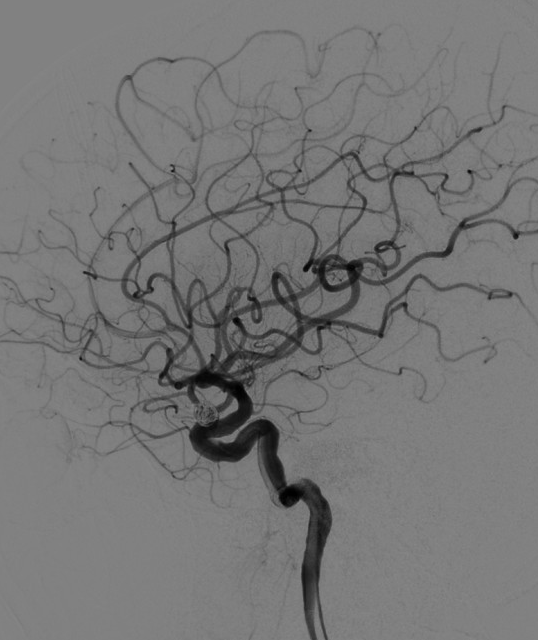

术前影像学检查CTA显示右侧颈内动脉海绵窦段巨大型动脉瘤。

术前3D显示右侧颈内动脉海绵窦段巨大型动脉瘤

DSA正位造影

DSA侧位造影